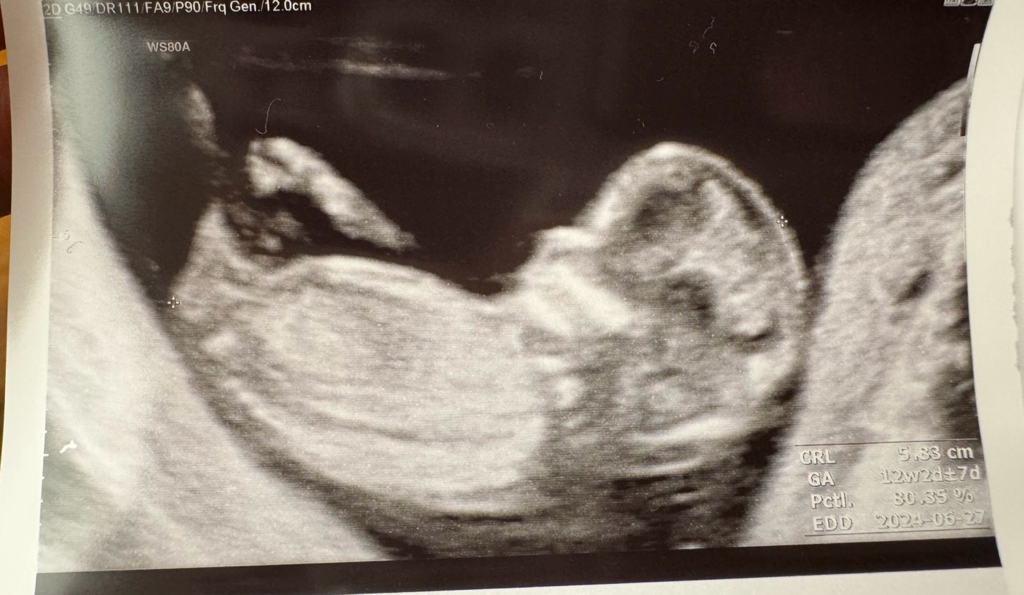

카페에서 보면 각도법으로 성별을 알수있다고 하는데

정확도가 높을까요??

어떻게 보는지 몰라 설명부탁드립니다.

사진으로 확인가능할까요~

임신12주경에는 병원에서 초음파 확인시 대충 파악 하기도 합니다.

태아의 성기부분이 하늘로 향하면 아들,평행하면 딸 이라는 각도법도 있습니다.